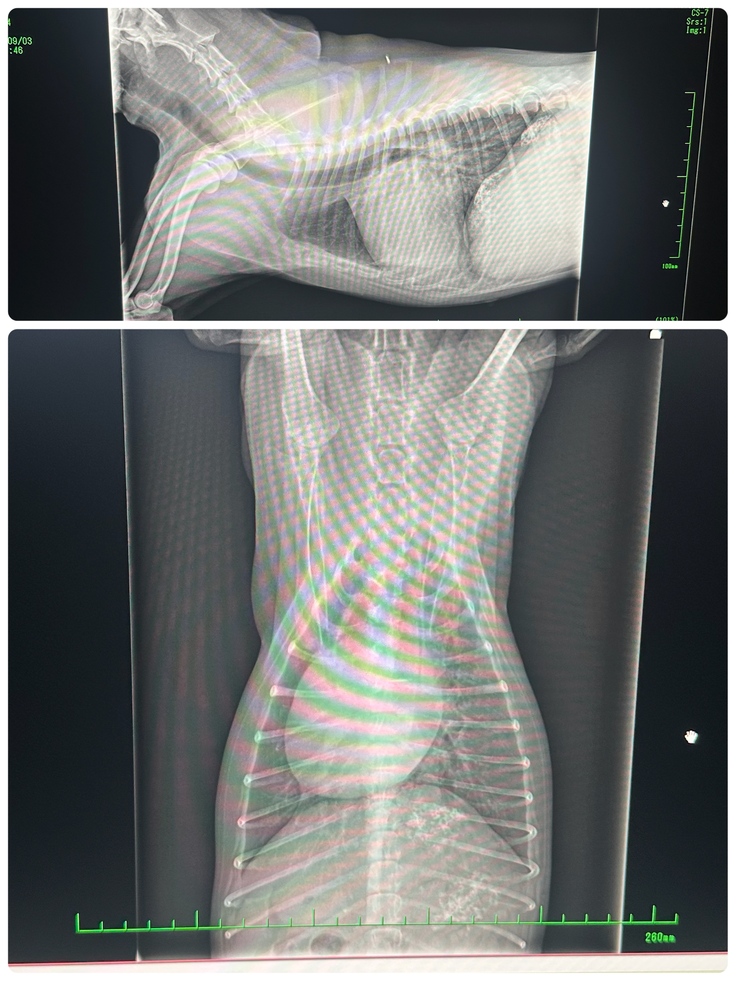

手術前検査

かかりつけ医から紹介していただいた大学病院にて手術することが可能なのか、いまの状態を検査してもらいました。

検査結果は手術適応。

9/3レントゲン心臓がかなり肥大している